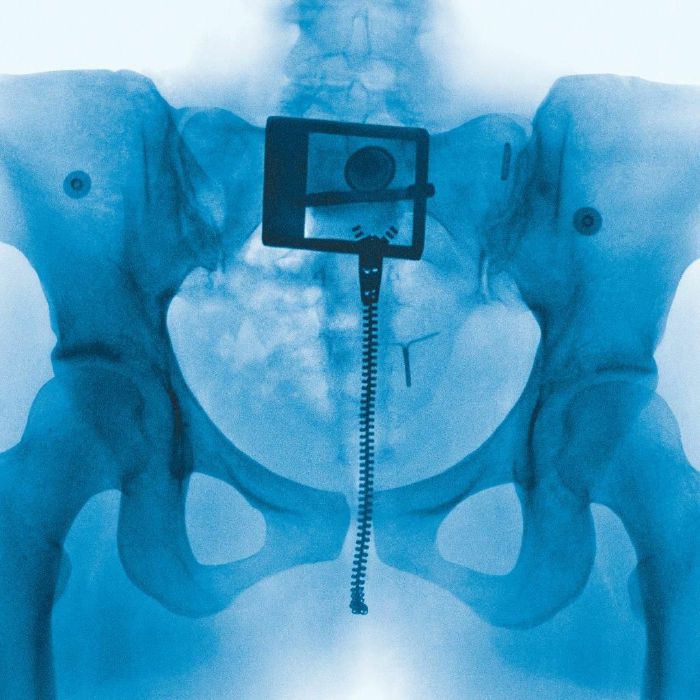

Lorde - Virgin

Virgin

Co-produced by Lorde and Jim-E Stack, with contributions from Devonte Hynes (Blood Orange), Dan Nigro, Fabiana Palladino, Buddy Ross, and Andrew Aged; Virgin is the sound of Lorde returning to the beat-driven and raw lyricism that propelled Pure Heroine and Melodrama to commercial and critical success.

Preceded by lead single “What Was That,” which peaked at #1 on the US Spotify Chart, Virgin marks the return of a truly generational artist.